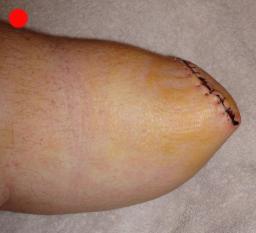

Postoperative (12th) images of left ankle

The images displayed here were created at various appointments following surgery performed by Dr. Daniel Saunders. In the X-Ray you can see

where Dr. Saunders has removed the fibula plate, joined the tibia and fibula with a screw, built-up the area of the tibia where previously

there was considerable absence of bone and lastly added the EBI OsteoGen-M Bone Stimulator (dual lead). The photos show the left side site

where the fibula plate was removed, the top site where donor bone, bone filler material and the stimulator were added and the right side

where the tissue has burst because of swelling. Liam was placed on an IV drip of Vancomycin following surgery to combat the potential onset

of Osteomyelitis. The image of the cast includes the fibula plate that was removed during surgery. The next images were taken later and show

that the staples and stitches were removed. In one of the images, you can see Liam's wife Madeline helping with leg cleanup and in one image

can be seen the EBI representative after being put to work (holding up the left leg while the latest cast cures) by Dr. Saunders. Later shots show

a healing tissue burst site with some overgrowth and Dr. Saunders cauterizing the overgrowth. Bones shifting too much (shown in X-Rays). The

last images are of the left ankle prior to the 13th surgery.